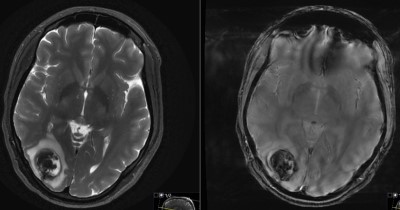

This is a 24 year old female who presented to the ER 2 years prior with first time seizure.

She has mild, intermittent visual disturbance